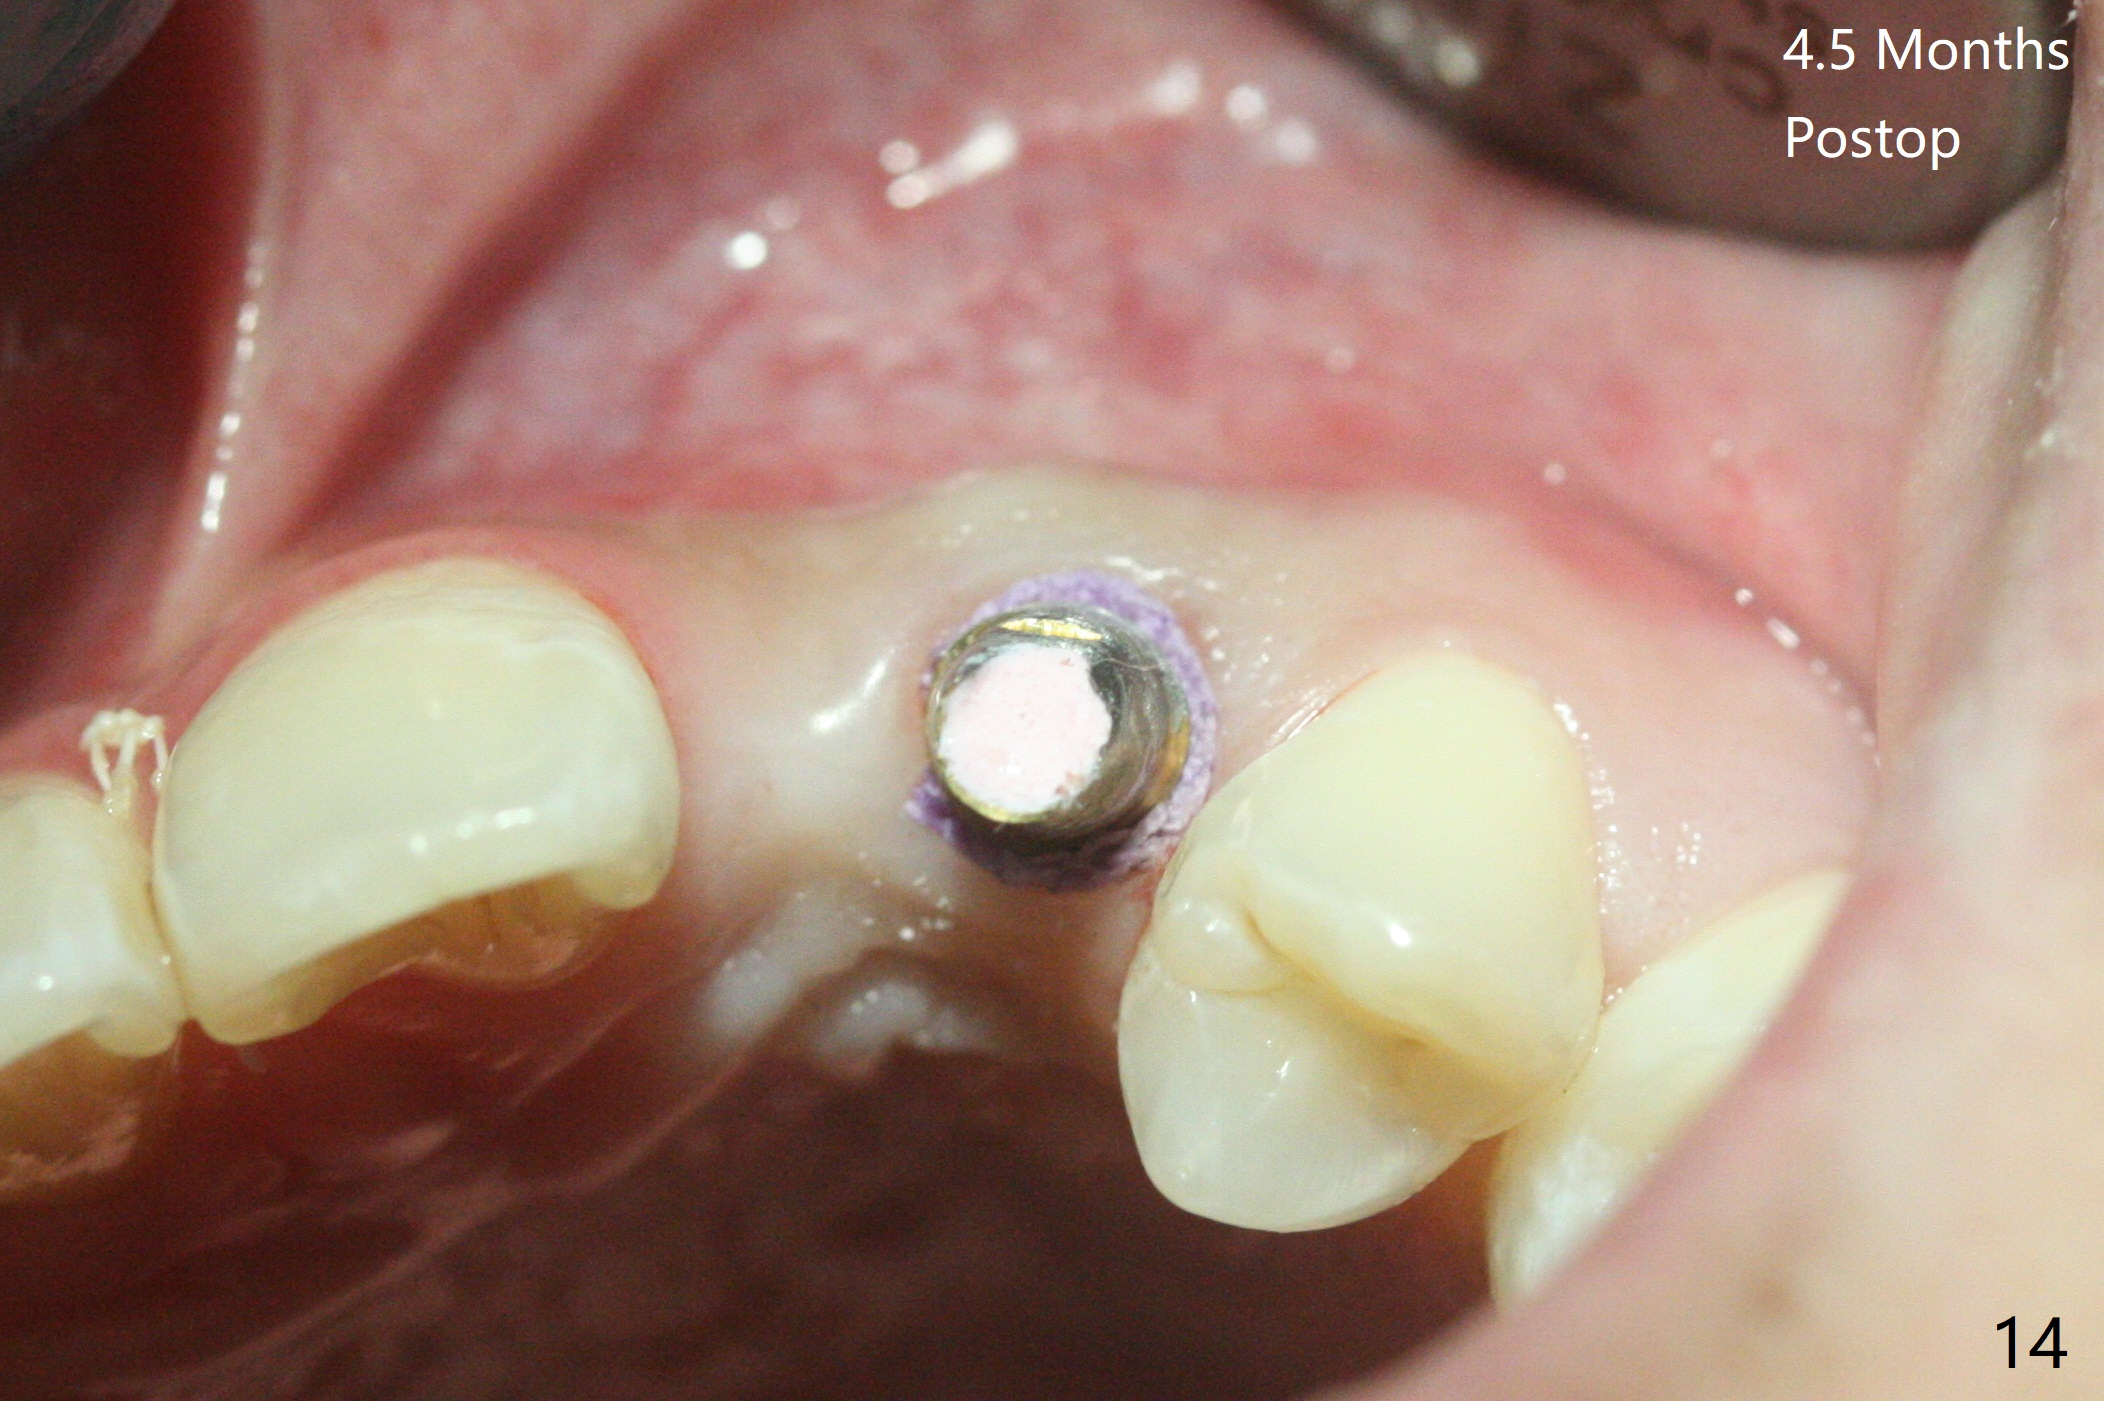

18岁男从外州大学回来,无症状,但是6号牙(右上尖牙)颊侧瘘道(图一,二(角化龈充分(箭头))),根尖片显示植体近中骨吸收(图三:*),而对侧植体仿佛骨整合(图四)。患侧切开后发现植体颊侧暴露,松动。拔除后骨缺损由粘性骨粉修复(图七,九:*),覆盖PRF膜(图七:P)和带钛网(图九:^)不可吸收膜(图五-七),后者用两个小钉子固定(图六(腭侧),七(颊侧),九),使用新的刀片和一个特殊尖头剥离器在颊侧骨膜下相当广泛分离,使用PTFE缝线,粘膜下水平褥式缝合之后(图八:箭头),多个垂直间断缝合,两个乳头垂直褥式缝合。术后一周伤口没有裂开,术后疼痛肿胀已经消退(图十)。术后十八天牙槽嵴仿佛比对侧还要宽(图十一,三与图十二,四(取模)对比)。术后5.5个月伤口没有裂开,牙槽骨,角化龈宽(图十六),与钛网和两个小钉子固定有关(图十五,十七)。CT显示牙槽骨只能容纳2.5或者3.0毫米植体(图十八)。11号牙植体牙冠粘固后没有骨质吸收(图十九),其实10,11号牙颊侧骨板隆起(图二十至二十二),而6植体失败,颊侧骨板吸收,甚至累及5号牙(图十七)。